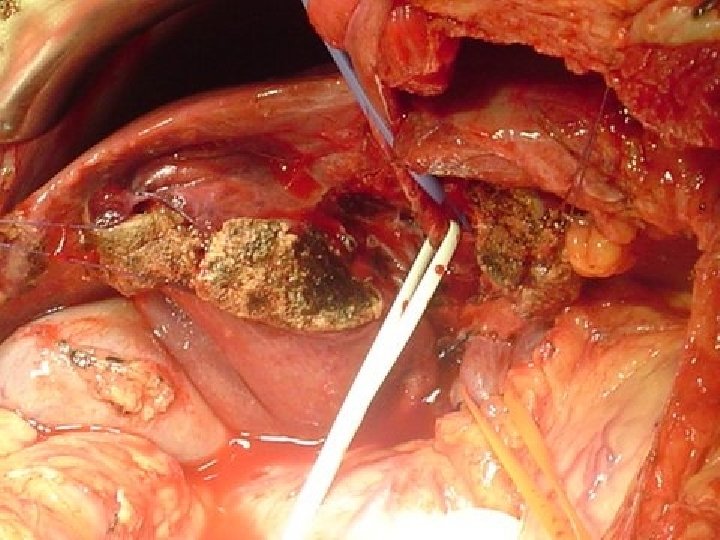

CONCEITO DO REX SHUNT MESO-LEFT PORTAL BY PASS 1 - LOCALIZAÇÃO PELO LIGAMENTO REDONDO DO FÍGADO DO RAMO ESQUERDO DA VEIA PORTA- INTRA HEPÁTICA 2 - DETERMINAR PATENCIA DO FLUXO PORTAL INTRAHEPÁTICO 3 - REALIZAR SHUNT MESENTÉRICO –PORTA ESQUERDA – JUGULAR- ILÍACA

Casuística pessoal – 12 casos n n Menino 9 anos – TVP Inúmeras internações por sangramento digestivo- 23 escleroterapias de varizes. Esplenectomia aos 3 anos Rex Shunt com jugular interna n Follow up- 5 anos - Sem complicações sem varizes esofágicas Otimo desempenho escolar n

Casuística pessoal – 12 casos n Menina 7 anos -TVP- inúmeras internações por sangramento digestivo- 32 escleroterapia de varizes. n Rex Shunt com jugular interna Trombose de Shunt com 6 mêses Novo Rex, com Ilíaca Interna Follow up- 4 anos Sem sangramento – Baço sp. Sem Varizes esofágicas Otima aprendizagem escolar. n n n